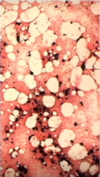

• Fat does not stain (will look like vacuoles)

Cellularity by Age

Fat vs Nucleated Cells

A

Adults

* 50% nucleated, 50% fat

Young

* 75% nucleated, 25% fat

Old

* 25% nucleated, 75% fat

9

Q

Define

BM Hypoplasia

Decreased number of cells

* <25% cellularity

* large areas of fat